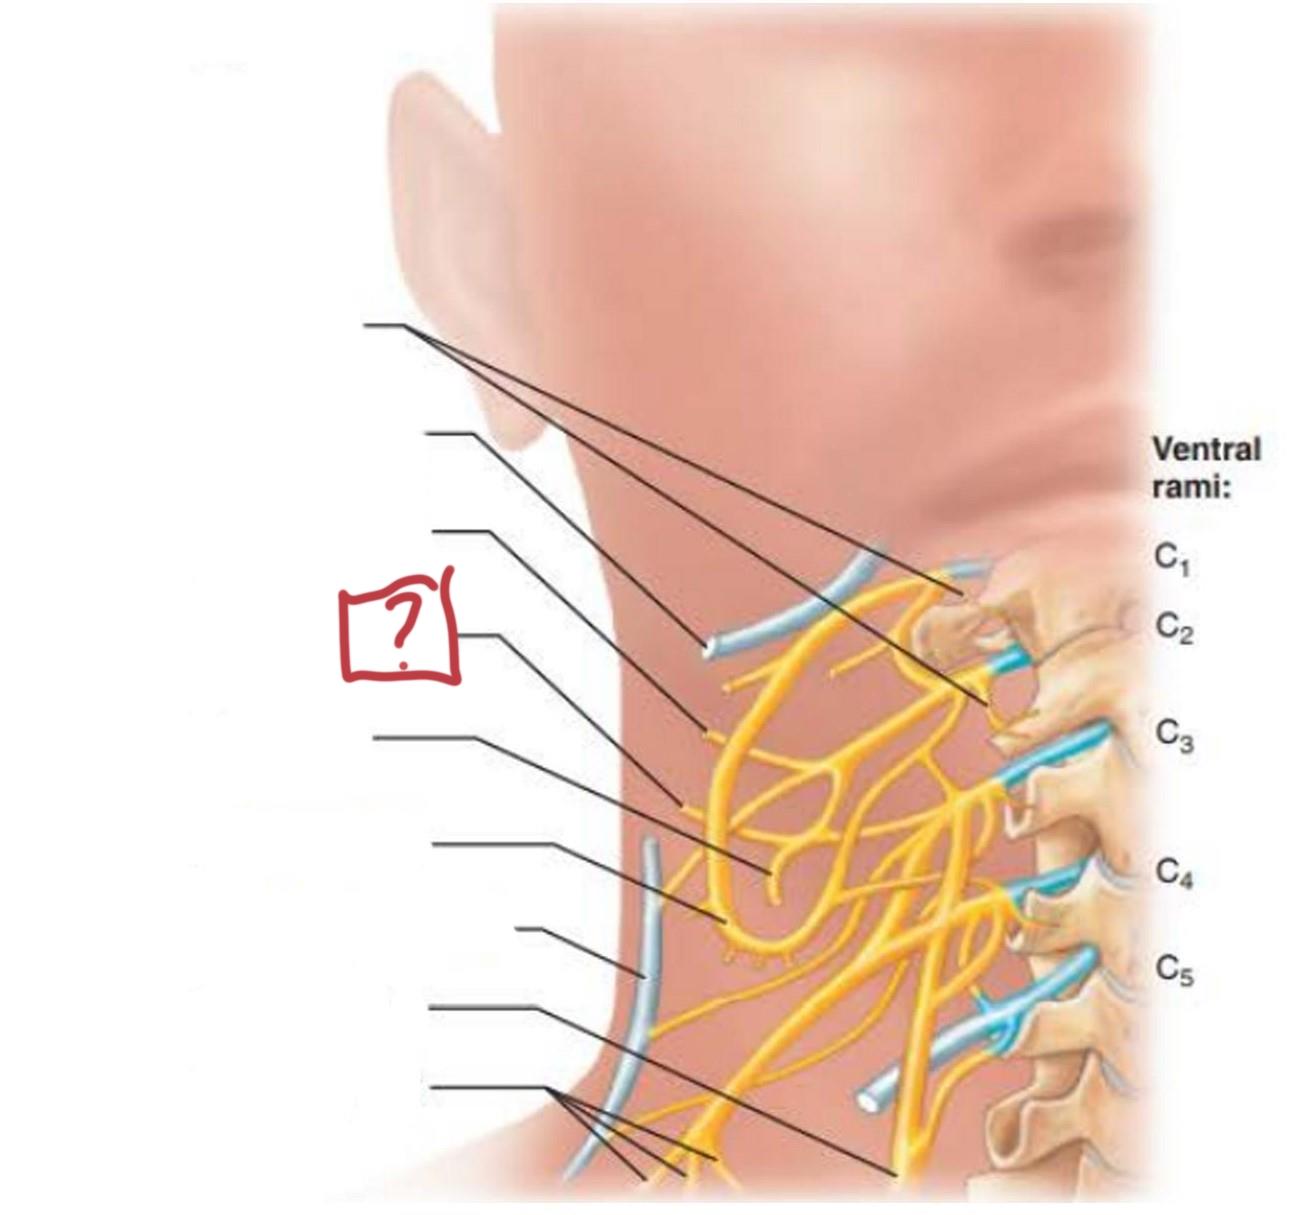

cervical plexus

C1-C4

segmental branches

hypoglossal nerve (12)

lesser occipital nerve

greater auricular nerve

transverse cervical nerve

ansa cervicalis

accessory nerve (11)

phrenic nerve

supraclavicular nerves